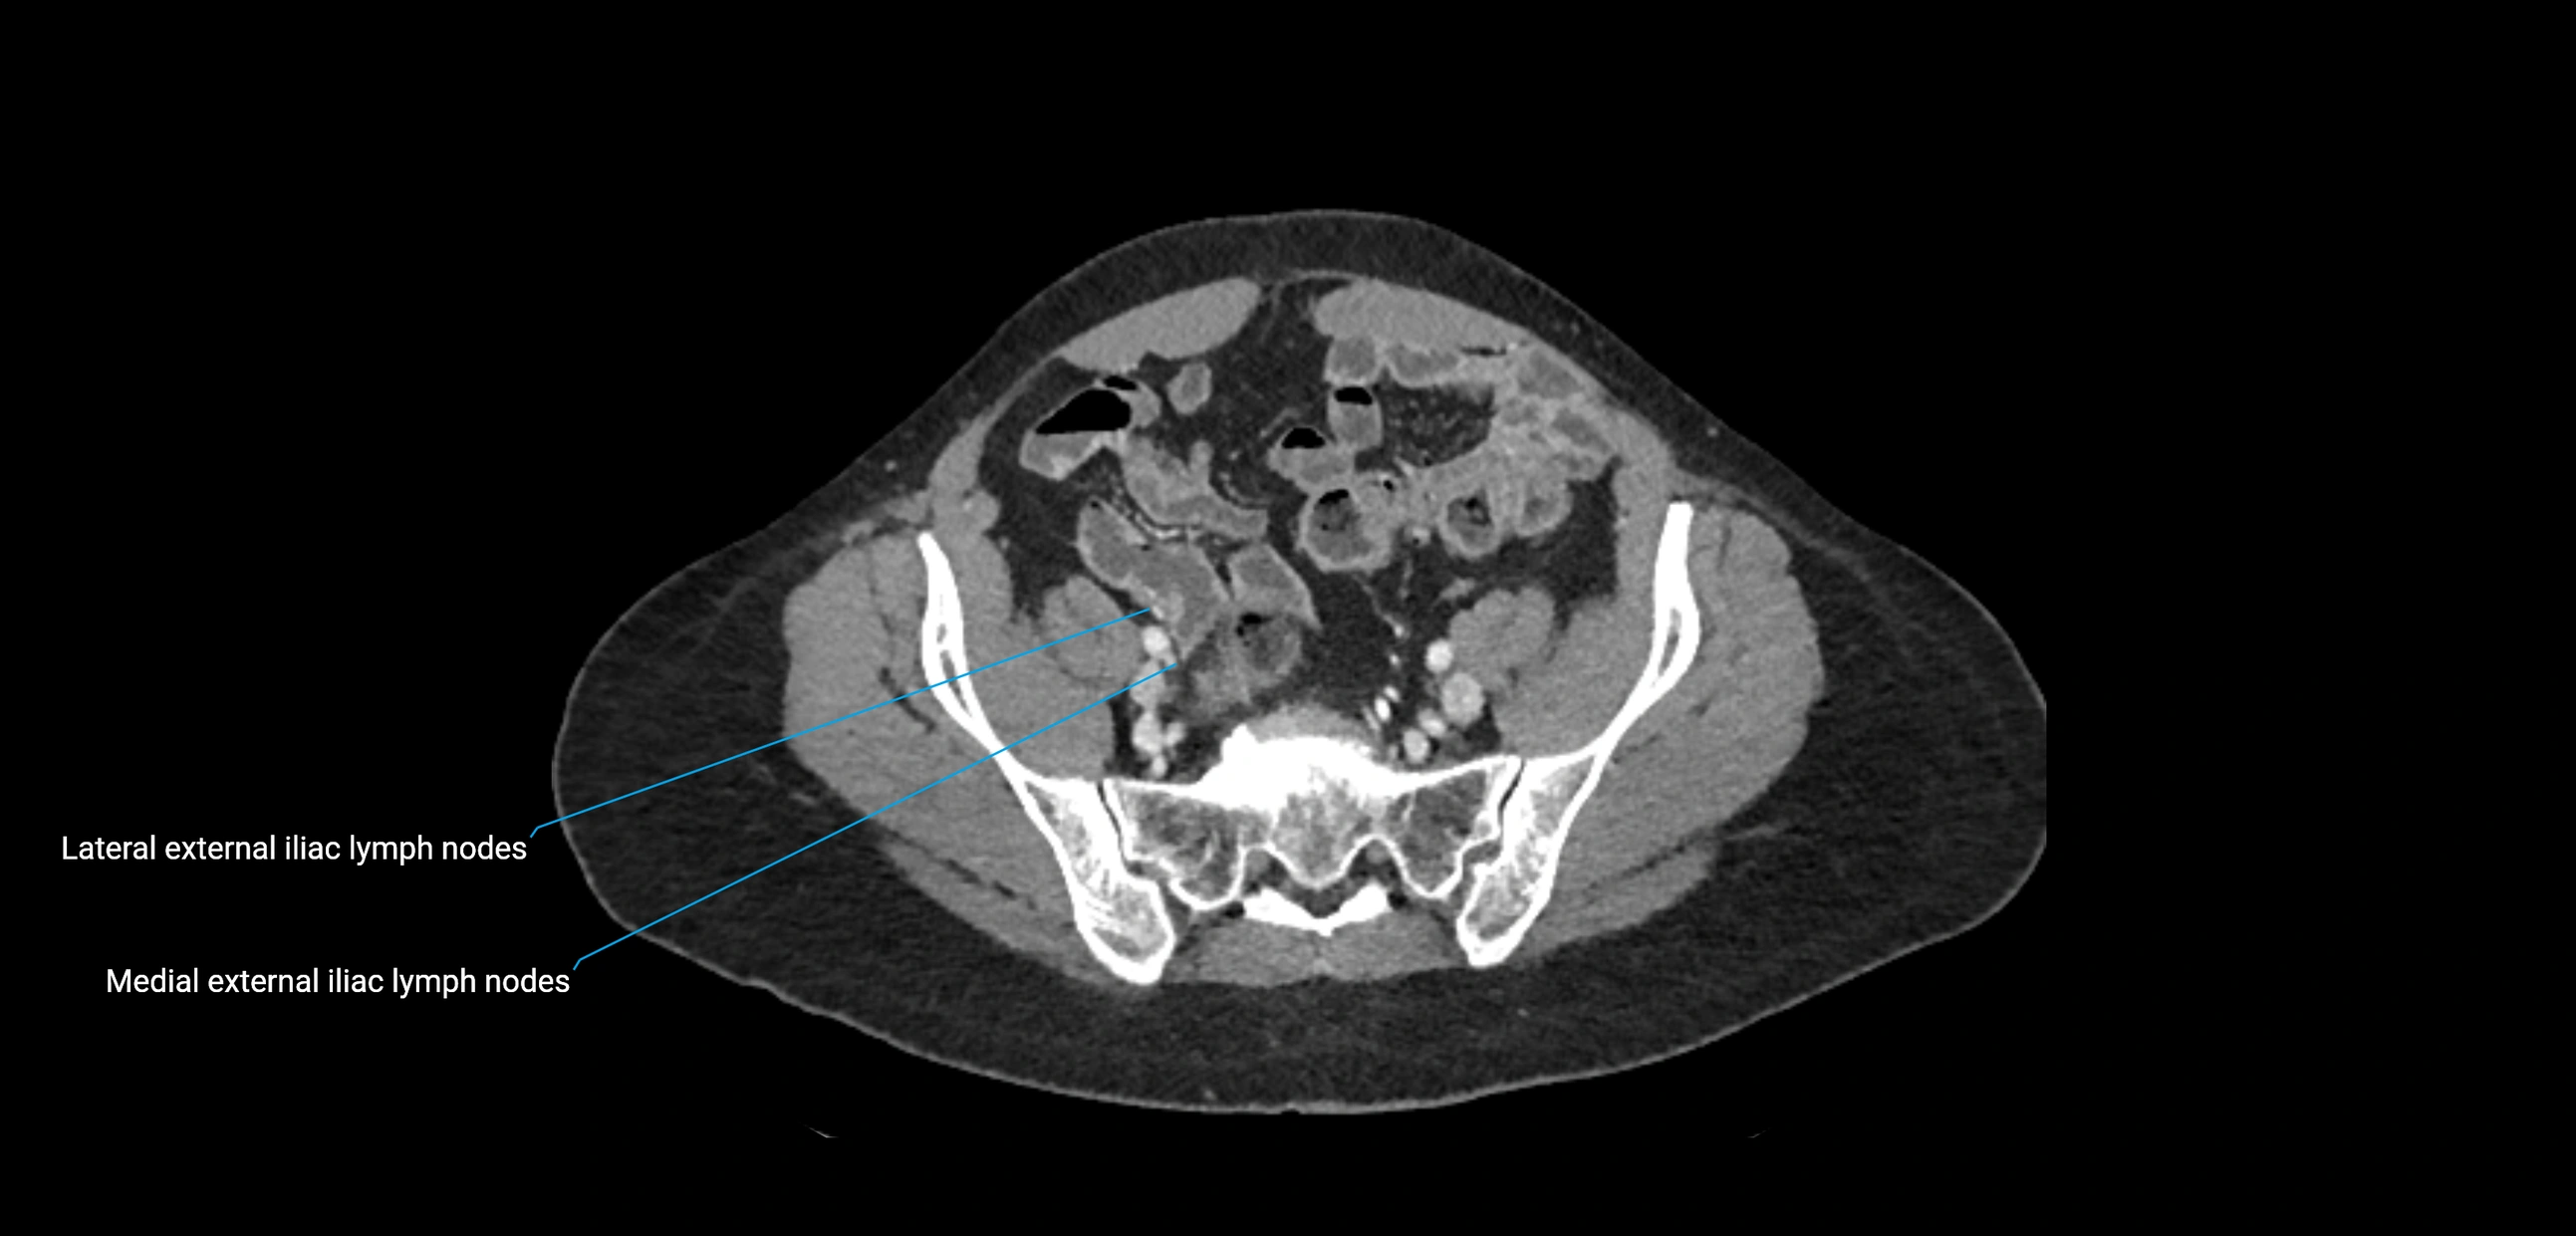

CT Appearance

CT Pre-Contrast:

• Nodes appear as soft-tissue density nodules adjacent to the aorta and IVC

• Calcification may be seen in chronic infections (e.g., tuberculosis)

CT Post-Contrast:

• Normal nodes enhance homogeneously

• Malignant nodes may show heterogeneous enhancement, central necrosis, or conglomerate formation

• Size >1 cm short axis is suspicious, though morphology and distribution are equally important